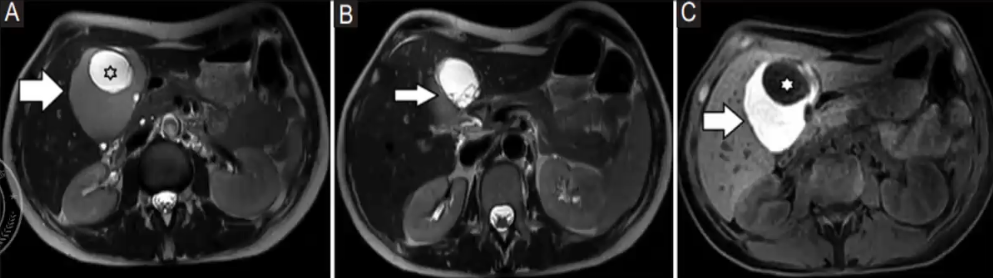

MR表现

❖ 典型的MRI特征包括:较大的多房性囊性肿块,T1WI呈低信号,T2WI呈高信号,囊壁厚且不规则,增强可见囊壁及分隔强化

❖ MRI对薄层分隔、内部出血、蛋白质碎屑、液液平面、与胆道相通伴上游胆管扩张等特征的显示更具优势